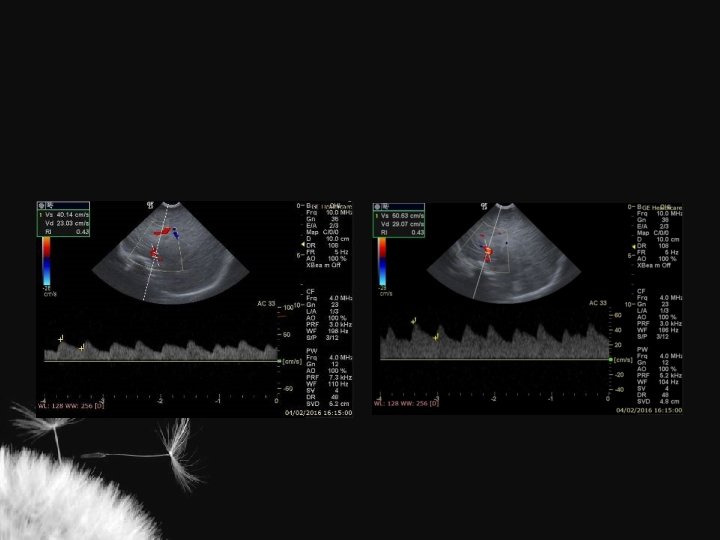

Artérias cerebrais normais

Valores normais ACI ACA AB Vs (cm/s) 50 + 15 42 + 15 41 + 16 Vd (cm/s) 11 + 4 11 + 5 11 + 4 TAMX (cm/s) 22 + 6 21 + 9 19 + 7 0, 77 + 0, 08 0, 73 + 0, 08 0, 72 + 0, 09 RI Deeg KH. Neuroradiology 32: 60 -63

Índice de resistência (IR) nas artérias intracranianas ACA ACI Martin (1982) 0, 75 + 0, 03 Jorch (1986) 0, 74 + 0, 06 Lipman et al. (1982) 0, 79 + 0, 04 Perlman et al. (1985) 0, 66 + 0, 06 Deeg (1989) 0, 73 + 0, 08 AB 0, 77 + 0, 07 0, 73 + 0, 06 0, 77 + 0, 08 0, 72 + 0, 09 ACA artéria cerebral anterior, ACI artéria carótida interna, AB artéria basilar IR pré-termo 0, 79 + 0, 02 IR > 2 anos 0, 50 + 0, 08